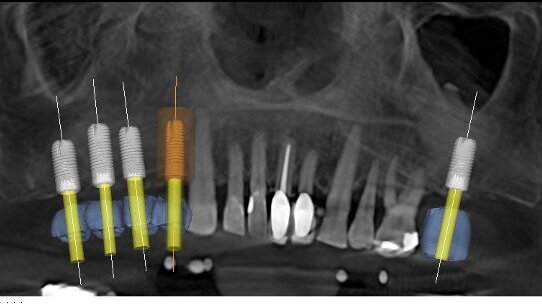

A stone study model was made, and the crown of tooth #10 was removed. This modified model was captured by CEREC in order to create a digital model that represented the site after tooth extraction. The opposing dentition was captured in a Futar D (Kettenbach) bite registration and the prosthetic proposal was created in CEREC (Fig. 3). The digital model and prosthetic proposal were then imported into GALILEOS. The ideal implant size and position were determined within the GALILEOS scan, based on the bony anatomy data, as well as the mucosal surface and prosthetic data from CEREC (Fig. 4). The treatment planning data, along with the stone model and a special scanning template were sent to siCAT, and a custom surgical template was returned.

This second case illustrates the tremendous power of the integration of GALILEOS and CEREC for treating the partially edentulous patient. This patient was a 62-year-old man with moderate bone loss due to smoking. He was otherwise healthy. He was missing teeth #2 to 5 and 15, and had undergone bilateral sinus-lift surgery to augment the bony deficiency in the posterior maxilla (Fig. 11). In preparation for implant placement, a GALILEOS CBCT scan was performed with a siCAT scanning template. A full-arch digital impression was acquired with the CEREC AC unit, and then prosthetic proposals were designed for teeth #2 to 5 and 15. This data was then imported into GALILEOS for implant planning (Figs. 12 & 13). The position of the implants was verified (Fig. 14) and the surgical guide was ordered from siCAT (Fig. 15). This was used to place four Astra Tech dental implants accurately using the Facilitate Surgical Guide (Astra Tech). Post-operative radiographs demonstrated that all four implants were accurately placed and in accordance with the treatment plan (Figs. 16 & 17). The patient had an uneventful post-operative course.